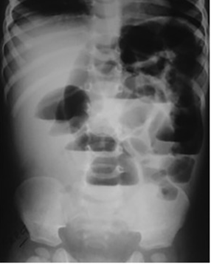

In infants under one year of age, the normal gas pattern on an abdominal X-ray appears honeycomb or polygonal shaped throughout the abdomen (Figure 1).3,4

Figure 1 Anteroposterior supine radiograph in a normal neonate on day-3 of birth showing honeycomb or polygonal gas pattern throughout the abdomen with gas visible in the rectum. It is difficult to differentiate small from large intestine in the neonatal period.